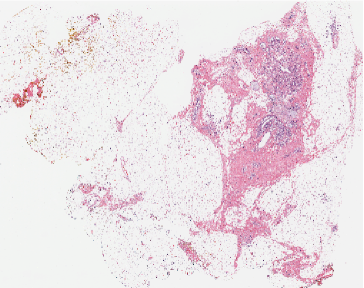

Figure 5: Grad-CAM visualization applied to a sample WSIs from Camelyon 16. Dark blue coloring indicates a low saliency, whereas red indicates a high saliency.

Figure 6: Grad-CAM visualization applied to a sample WSIs from TUPAC16. Dark blue coloring indicates a low saliency, whereas red indicates a high saliency.

According to the Gradient-weighted Class Activation Mapping (Grad-CAM) method proposed in paper [18], the spatial position of visual cues relevant in predicting the image-level labels of some WSI samples are shown in Figures III-C and  III-C. In particular, Figure III-C shows comparisons of the saliency maps with fine-grained manual annotations of some examples of WSIs of Camelyon16, while Figure III-C reports some examples for TUPAC16. It is worth to notice that in tumor WSIs our model focuses on very specific areas corresponding to active tumor regions. Additionally, the saliency maps might be exploited by pathologists as a suggestion of regions that need to be analyzed more carefully.